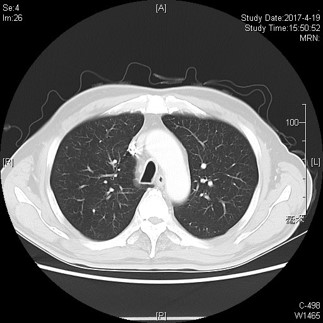

影像学检查:

胸部及腹部增强CT检查提示“结肠癌术后,吻合口周围肠系膜结构致密,见斑片索条影,腹壁切口肿胀,未见明显强化结节,以上均拟术后改变为主;左下肺见斑片,暂拟炎性病灶。”

2015-05-08 CT示:左下肺结节,较前稍增大,实性成分较前稍增多,拟转移可能。

2015-09-23CT:左下肺结节,较前增大,拟转移;结肠术区肠系膜结构致密,见斑片索条影,较前变化不大,仍考虑为术后改变;盆腔积液较前减少。